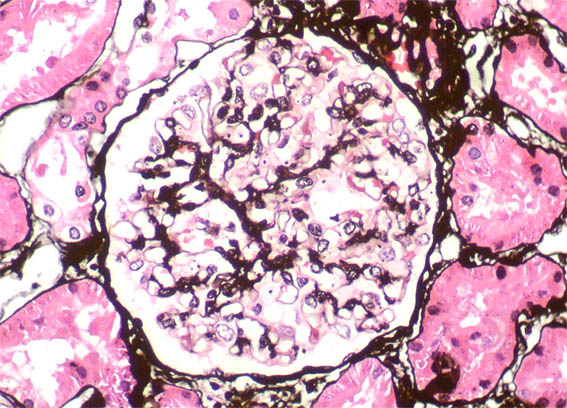

Figure 5. Methenamina-silver stain, X400.